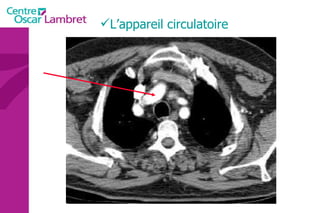

L’appareil circulatoire L’appareil circulatoire  s’appuie sur un véritable réseau aussi étendu que précis. Sous l’impulsion du  coeur , chef d’orchestre vital, les artères et les veines assurent le transport du sang indispensable à tout notre organisme.  Les artères  apportent le sang riche en oxygène et en nutriments à l’ensemble des tissus de l’organisme.  Les veines  doivent rapporter le sang appauvri en oxygène vers le coeur puis les poumons. Des  poumons , il repasse dans le coeur qui le propulse de nouveau via les artères à tout l’organisme.

La circulation sanguine , Les différents rôles : Poumons  : fournir l’O2 et rejeter le CO2 Cœur  : pompe Foie et intestin  : 1/3 du sang passe par les capillaires de l’intestin et se charge de produits de la digestion les quantités sont régulées par le foie. Reins  : élimination des substances nocives et des déchets par voie urinaire.